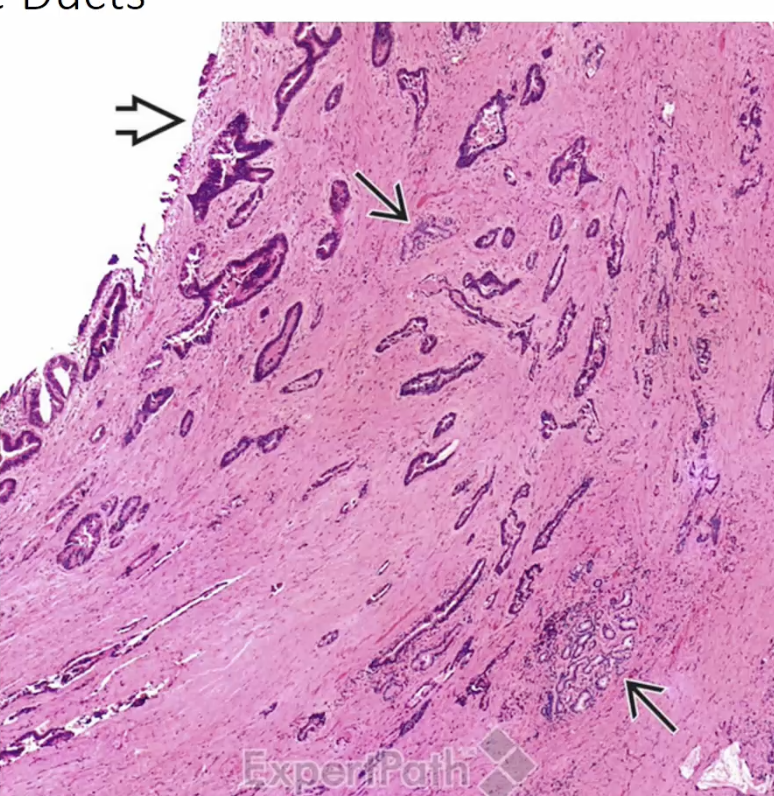

Chronic cholecystitis

Rokitansky-Aschoff Sinuses

small pouches that form in the gallbladder wall, often associated with chronic cholecystitis. They can contribute to inflammation and dysmotility of the gallbladder.